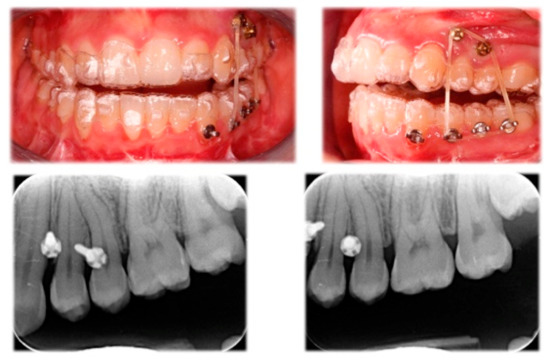

2.2. Treatment Progress